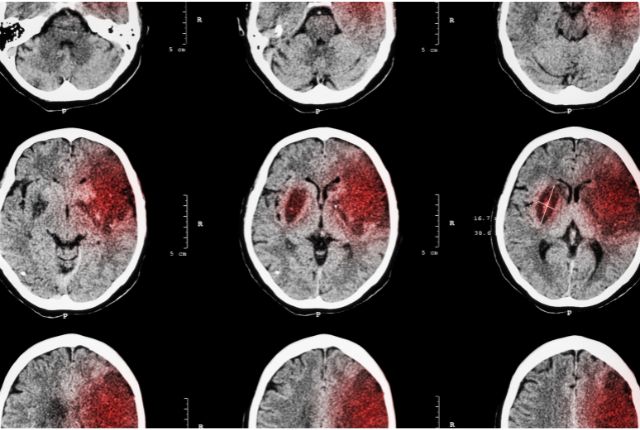

Accident Vasculaire Cérébral

L’accident vasculaire cérébral ou AVC, ou encore infarctus cérébral, désigne un arrêt brutal de l’irrigation sanguine d’une partie du cerveau. En cause, une artère bouchée par un caillot ou un vaisseau sanguin qui se rompt au niveau du cerveau. Les AVC sont la 2e cause de mortalité en France selon l’INSERM. Soyez informé des symptômes, des causes, des traitements et des moyens de prévention d’un accident vasculaire cérébral.

L’AVC hémorragique

L’AVC hémorragique est le type d’AVC le moins fréquent : 15 à 20 % des cas d’AVC. Il concerne les accidents vasculaires cérébraux dus à une rupture d’un vaisseau sanguin au niveau cérébral. Par vaisseau sanguin, on entend ici une veine et non une artère. Il s’agit dans la majorité des cas d’une rupture d’anévrisme, mais une tumeur, l’hypertension, des problèmes de coagulation peuvent aussi en être à l’origine.